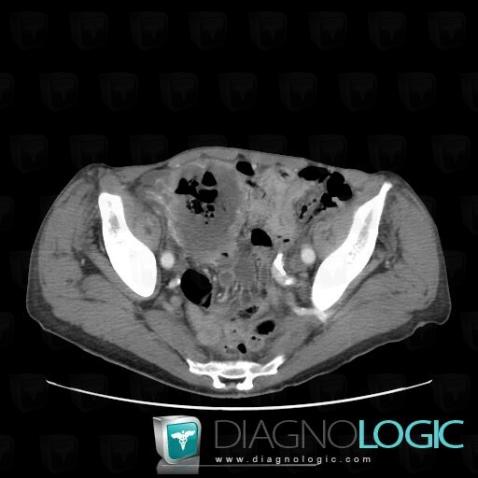

Lymphoma, Retroperitoneum, CT

Here is the specific information in the key image above:

- Diagnosis Lymphoma, Location(s) Retroperitoneum, with gamuts Retroperitoneal lymphadenopathy